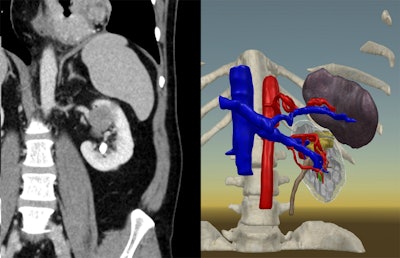

To determine the potential advantages of planning with 3D models, Shirk and colleagues obtained the MRI or CT scans of 92 kidney cancer patients scheduled to undergo robotic-assisted partial nephrectomy. They used the scans to generate individually tailored 3D kidney models for roughly half of the patient cohort. Each of the 3D models comprised at least the kidney tumors and renal vasculature, and most included several other structures such as the ureter, collecting duct system, and splenic vasculature.

The surgical team completed presurgical planning for each case either using the conventional method of inspecting just the patient MRI and CT scans or examining the MRI and CT scans in addition to viewing the 3D models on a smartphone and VR headset. The smartphone and VR devices allowed the clinicians to rotate and expand the 3D models as well as reveal or hide specific anatomical structures to better visualize the ideal surgical route.